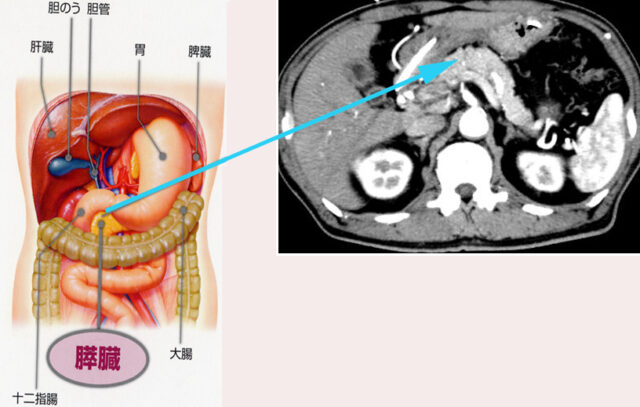

厚さは約2cmで、門脈や大動脈といった血管や胆管に囲まれた臓器です。膵臓の役割は、食物の消化(膵液の分泌)、胃酸の中和、血糖調節(ホルモンの分泌)です。

膵臓は胃の裏側にあるため病気が見つけにくく、検査も難しい臓器です。